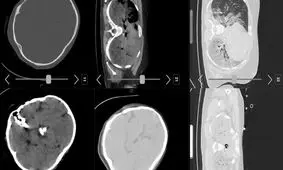

صبح امروز شبکه اینترنشنال وابسته به عربستان سعودی عکسی از سیتی اسکن مرحوم مهسا امینی منتشر کرد و مدعی شد که «سیتی…